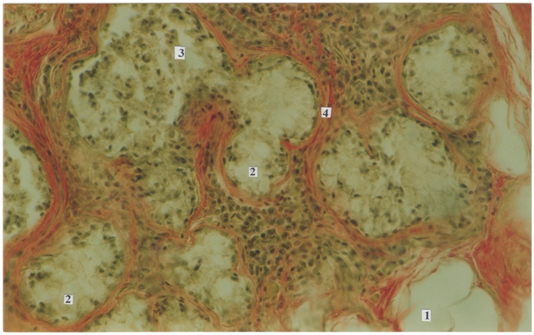

Статья имеет целью изучение железисто-лимфоидных взаимоотношений пищеварительного тракта в постнатальном онтогенезе и представляет особый интерес для клинической иммунологии. Макроскопическим и гистологическим методом нами исследованы слюнные железы, полученные от трупов 299 человек (язычные железы), начиная от новорожденных и до периода долгожительства, исследованы трупы представителей мужского и женского пола. Материал забирали в судебно-медицинских моргах Бюро СМЭ Департамента здравоохранения г. Москвы, что разрешено Постановлением Правительства РФ, Федеральный закон № 323, ст. 47, 4180-1, 355н. В фактический материал для исследования не включали случаи, когда при судебно-медицинском исследовании трупа выявляли патологические изменения пищеварительной системы. Микропрепараты (поперечные срезы) были окрашены гематоксилином-эозином и пикрофуксином по ван Гизону.

Малые слюнные железы, язычные и глоточные, располагаясь в толще языка и стенках глотки, выполняют важную эндокринную функцию – участвуют в обеспечении реакций местного иммунитета в ротовой полости. Множество публикаций посвящено регенеративным изменениям слизистой оболочки рта под действием секреторного иммуноглобулина А, который выполняет основную роль в регуляции местного иммунитета. В статье отражены важные аспекты возрастных изменений малых желез (язычных и глоточных). Характерная немногочисленность желез в детском возрасте обусловлена однотипностью питания в данном возрастном периоде, а снижение выработки секреторного иммуноглобулина А закономерно ведет к возникновению частых воспалительных процессов в полости рта и глотки. С возрастом устья желез расширяются и увеличивается их количество, что влечет за собой усиление местного иммунитета в ротовой полости и ротовой части глотки. Начиная с пожилого и старческого возраста наблюдаются инволютивные изменения, которые сопровождаются снижением выработки секреторного иммуноглобулина А и, соответственно, снижением показателей местного и гуморального иммунитета. Эти результаты полностью отражают топографические взаимоотношения желез с клетками лимфоидного ряда, и приведенные данные весьма актуальны для клинической иммунологии.